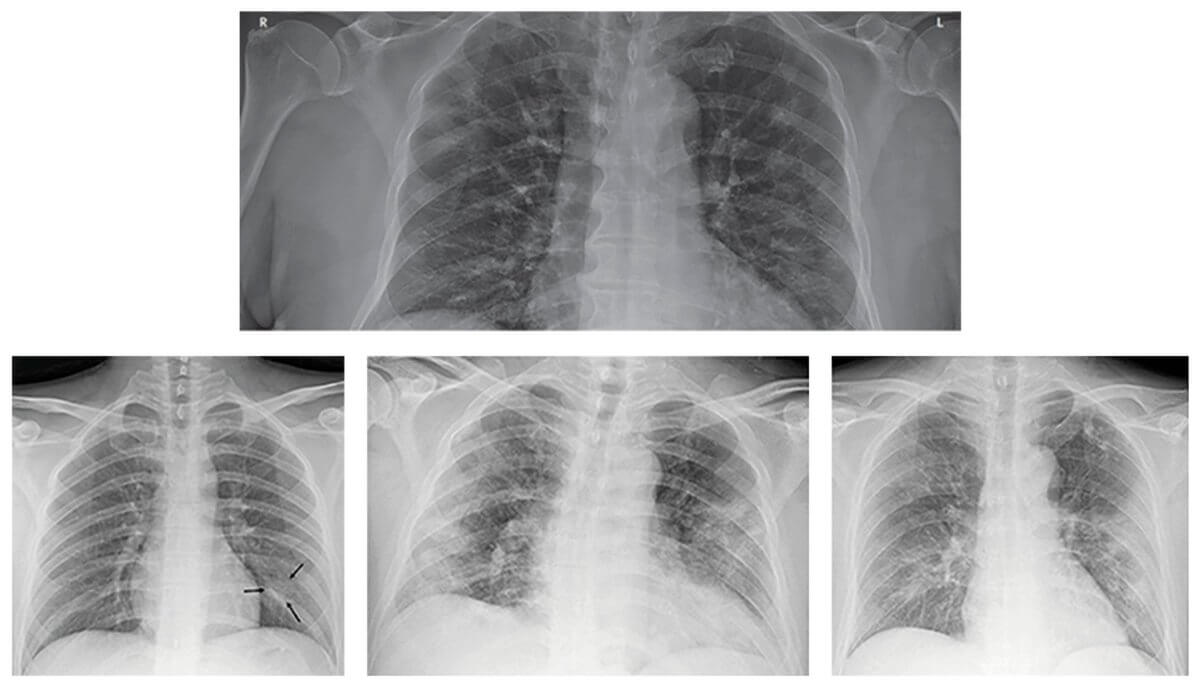

Рентгенография позволяет выявить специфические изменения в легочной ткани. На снимках зараженного человека есть совокупность признаков, которая говорит о заражении коронавирусной инфекцией.

На снимках проявляется усиление легочного рисунка, узловатые затемнения воздушных путей, могут появляться локальные уплотнения. И также, как на КТ-снимке, врач рентгенолог может увидеть синдром «матового стекла» и эффект «булыжной мостовой». Рентген показывает периферические локализации, которые, как правило, располагаются ближе к грудной клетке и дальше от сердца.

Вот как описывают изменения на рентгенографии доктора, работающие в больницах Гонконга с января 2020 года:

Несмотря на высокую специфичность и чувствительность КТ, в сложившихся условиях рентгенография имеет ряд неоспоримых преимуществ. Рентгеновское исследование занимает гораздо меньше времени, чем компьютерная томография, а специалист в случае сомнения в интерпретации результатов всегда может отправить пациента на КТ.